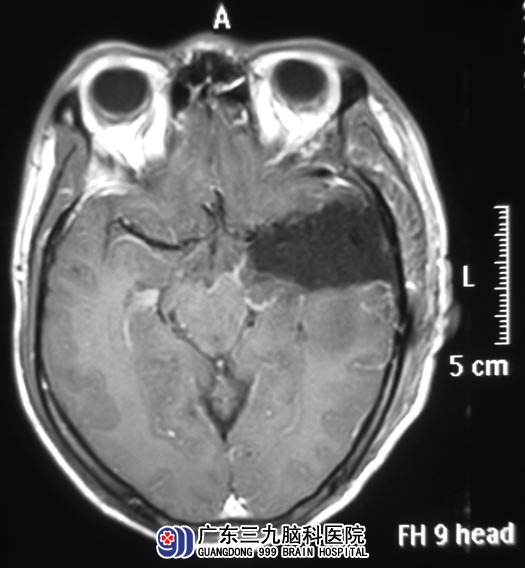

家人为了弄个明白,带着他去医院,头颅MR检查提示:左侧颞叶巨大占位性病变。

完成相关检查后,由广东三九脑科医院综合神经外科 鲁明主任主刀,在唤醒麻醉下行左侧颞叶占位切除术,显微镜下见颞叶脑组织膨胀,肿瘤与丘脑、中脑、桥脑粘连。在语言及肢体活动保护完好的情况下将肿瘤全切。术后叶先生的语言及肢体运动功能完好,记忆力、理解力都明显好转。病理结果为:胶质母细胞瘤(WHO IV级)。